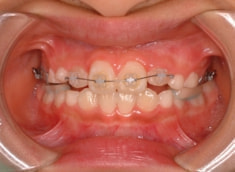

治療後(1年7ヶ月後)

治療開始から約1年1ヶ月後

フェイスマスクによる上顎の前方牽引の効果が認めらます。

治療前後の重ね合わせから、フェイスマスクの効果が認められます。

フェイスマスクの効果が得られております。